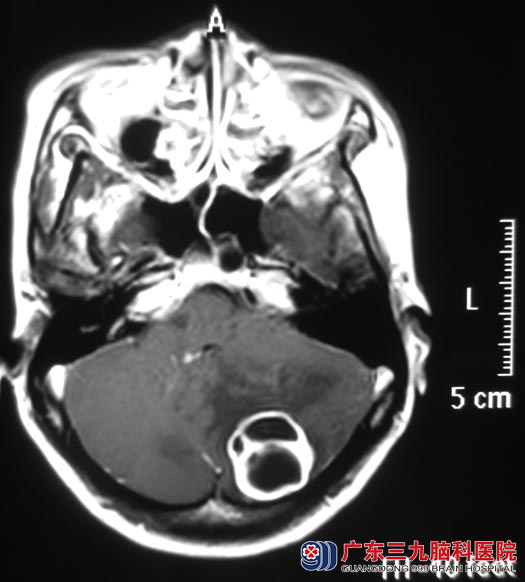

占女士一向身体健康。二个月前开始出现头晕,程度轻,没有头痛、呕吐、走路不稳等症状,间断性发作。为慎重起见,她在家人的陪伴下去医院检查,头颅CT检查提示:左侧小脑低密度病灶,脑组织肿胀。http://www.999brain.com/

广东三九脑科医院头颅MR检查提示:左侧小脑半球囊性病灶,大小约28.3mm×28.3mm×23.5mm。